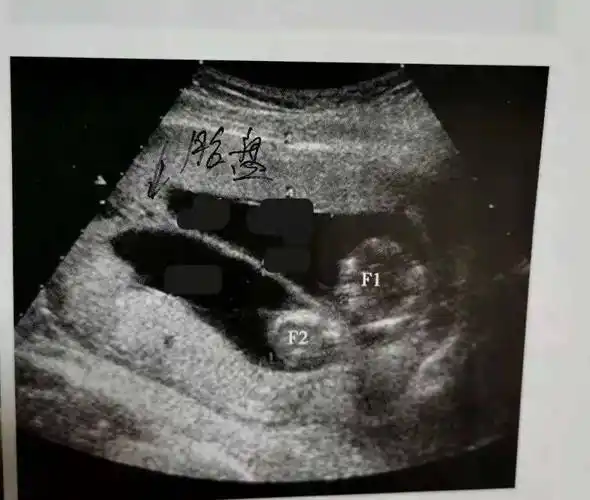

球拍状胎盘声像图

【读片】球拍状胎盘,合并完全性胎盘前置 - 超声医学讨论版 -丁香园